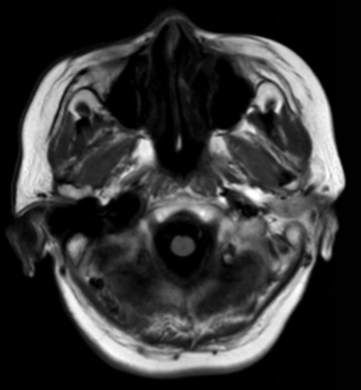

术后复查MRI: